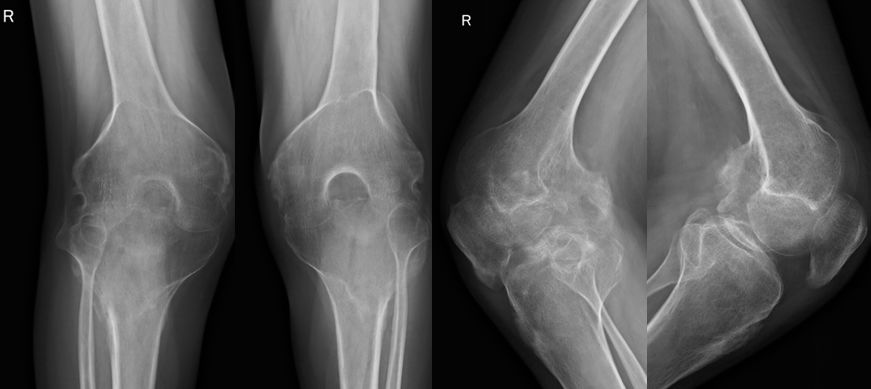

例2:29岁男性,AS患者,双髋、双膝关节疼痛伴活动受限6年